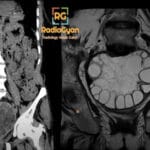

32 yr female presenting with subacute motor weakness and sensory disturbances.

Diagnosis: Multiple sclerosis

- MRI: T2/FLAIR hyperintense lesions in periventricular, juxtacortical, infratentorial, and spinal cord regions; chronic lesions appear as T1 hypointense “black holes”; active lesions show variable gadolinium enhancement; spinal lesions are typically short-segment (less than 2 vertebral levels).

- Signs: Dawson’s fingers (ovoid lesions perpendicular to ventricles); Open-ring enhancement (incomplete enhancement favoring demyelination over tumor); Central vein sign (vein within lesion on susceptibility-weighted imaging); Black holes (axonal loss).